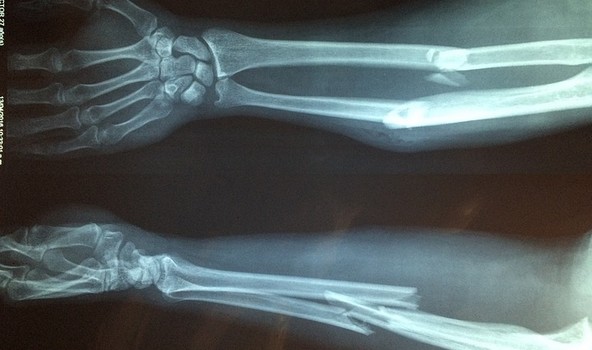

Nedir?: Kırıkları açık ve kapalı kırık diye ikiye ayırıyoruz. Kapalı kırıkta kırık üzerindeki deri bütünlüğü bozulmadığı halde açık kırıkta deri bütünlüğü bozulmuş ve kemik ucu dışarıdan görülmektedir.

Kırık kemiğin ucuyla damar yırtılırsa açık kırıklar aşırı kan kaybına neden olur. Dış çevrenin kirli ortamı ile teması nedeniyle iltihaba neden olabilirler.

Tedavi: Açık kırıklarda acil yapılması gerekenler şunlardır: Öncelikle kanama mevcutsa bu kontrol altına alınmalıdır. Daha sonra debridman denilen ölü dokuların ve yabancı cisimlerin ortamdan uzaklaştırılması ilk yapılacak işlemdir ve mutlaka steril şartlarda yapılmalıdır. Debridman işleminden sonra bu bölge bol serum fizyolojik ile ölü doku kalmayıncaya kadar yıkanmalıdır. Eğer yara yeri dikiş atılarak kapatılabiliyorsa kapatılmalıdır. Daha sonra kemikteki kırık alçı, traksiyon veya içerden ve dışarıdan konulan implantlar yardımı ile tespit edilmelidir. Enfeksiyon riski yüksek olan açık kırıklarda geniş spektrumlu antibiyotikler kullanılmalıdır. Antibiyotiğin verilme süresi açık kırığın durumuyla ilgilidir. Yine açık kırıklarda erken dönemde genel enfeksiyon, tetanoz, gazlı gangren gibi öldürücü tablolarla karşılaşılabilir. Böyle durumlarda amputasyon denilen o bölgenin vücuttan alınması kurtarıcı bir ameliyattır.